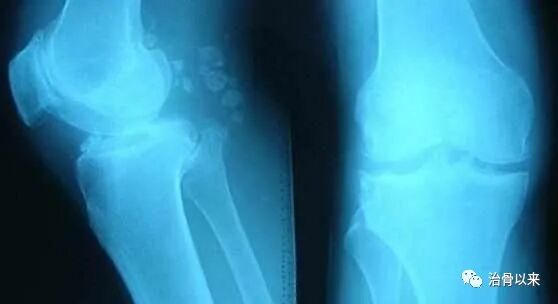

到医院拍片,影像显示在膝关节外侧下方有一游离体,故诊断上述症状是游离所致,属于骨质增生,俗称骨刺,建议让手术取出此物,消除不适症状。